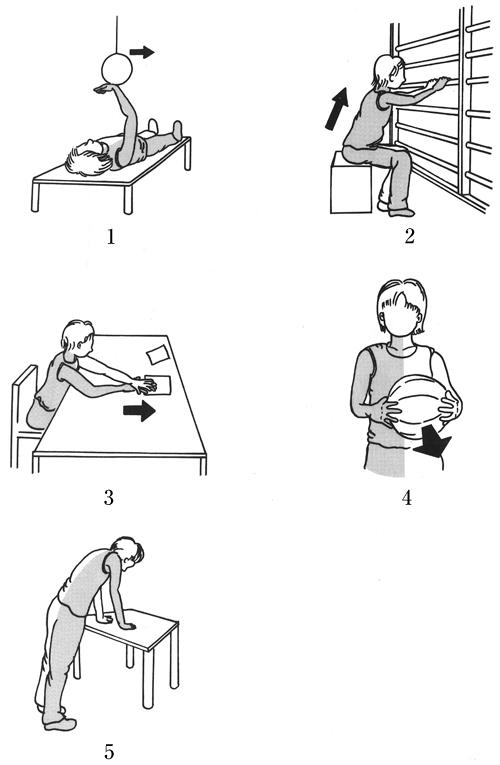

68歳の女性。発症後2か月の脳卒中右片麻痺患者。Brunnstrom法ステージは上肢Ⅳ。上肢の伸筋群に随意的な関節運動が認められるようになった。肘伸展を誘発するための作業療法で適切でないのはどれか。

1

1

2

2

3

3

4

4

5

5